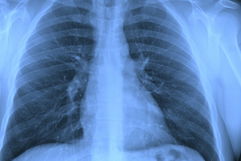

La ventilación mecánica es el uso de máquinas para ayudar a la persona a respirar. Esta está indicada cuando las vías aéreas y la ventilación están comprometidas o cuando la persona tiene insuficiencia respiratoria grave.

La ventilación mecánica facilita el flujo de aire a los pulmones y puede ser invasiva, siendo realizada a través de una traqueostomía o intubación orotraqueal, o no invasiva, utilizando mascarillas de ventilación.

El ventilador mecánico actúa moviendo el oxígeno hacia el interior los pulmones y removiendo el dióxido de carbono de la respiración.

Por utilizar una máquina para promover el flujo de aire en los pulmones, el uso del ventilador mecánico a menudo se describe como "respirar con ayuda de aparatos".